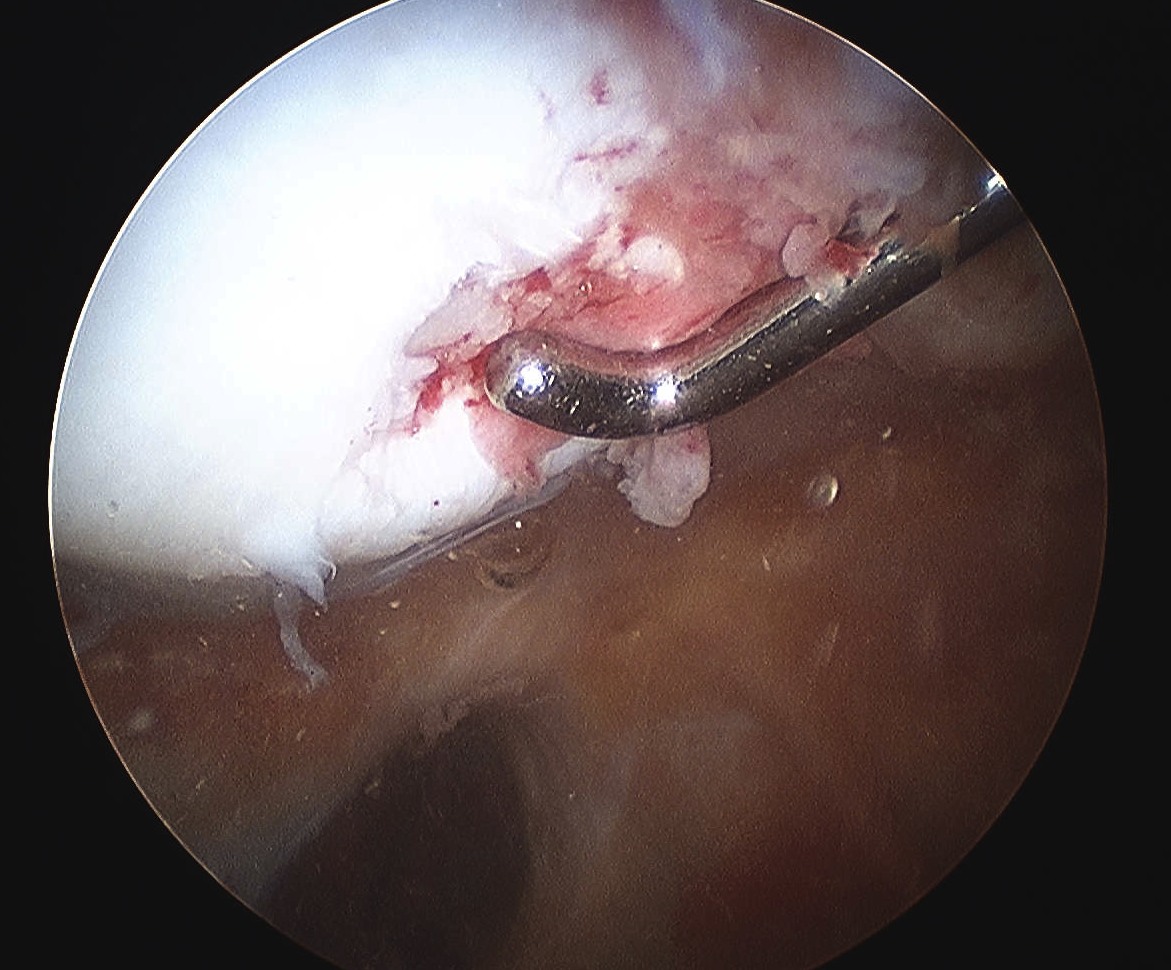

Arthroscopy

Assess Patella and Femoral Lesions

1. Small pieces cartilage

- remove loose bodies

- microfracture if necessary